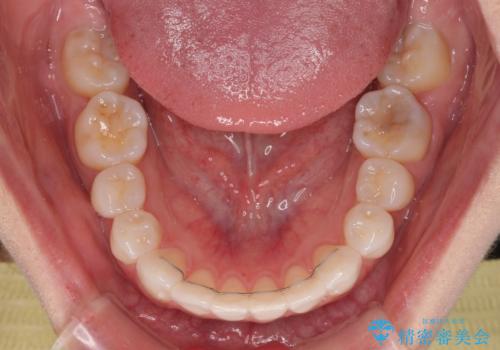

奥歯の咬み合わせを維持しながら正中位置を改善するために、補助装置を使用しました。

予定より期間がかかりましたが、上下の正中位置を綺麗に一致させることができました。